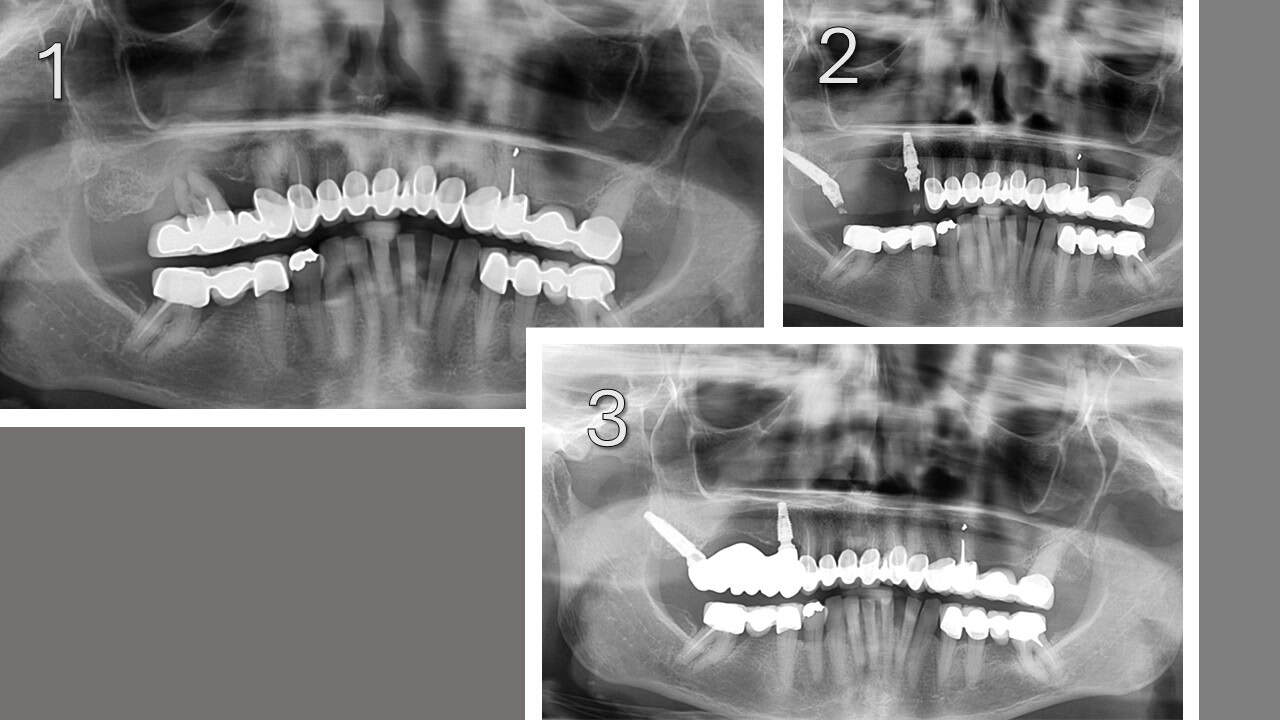

Examples of pterygoid implant placement